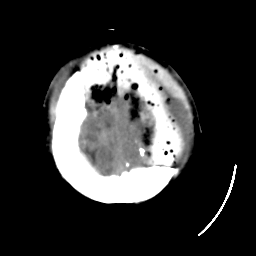

Meningioma: Roentgen-ray CT #1 -- Slice #21

[Home][Help][Clinical] Slice 21